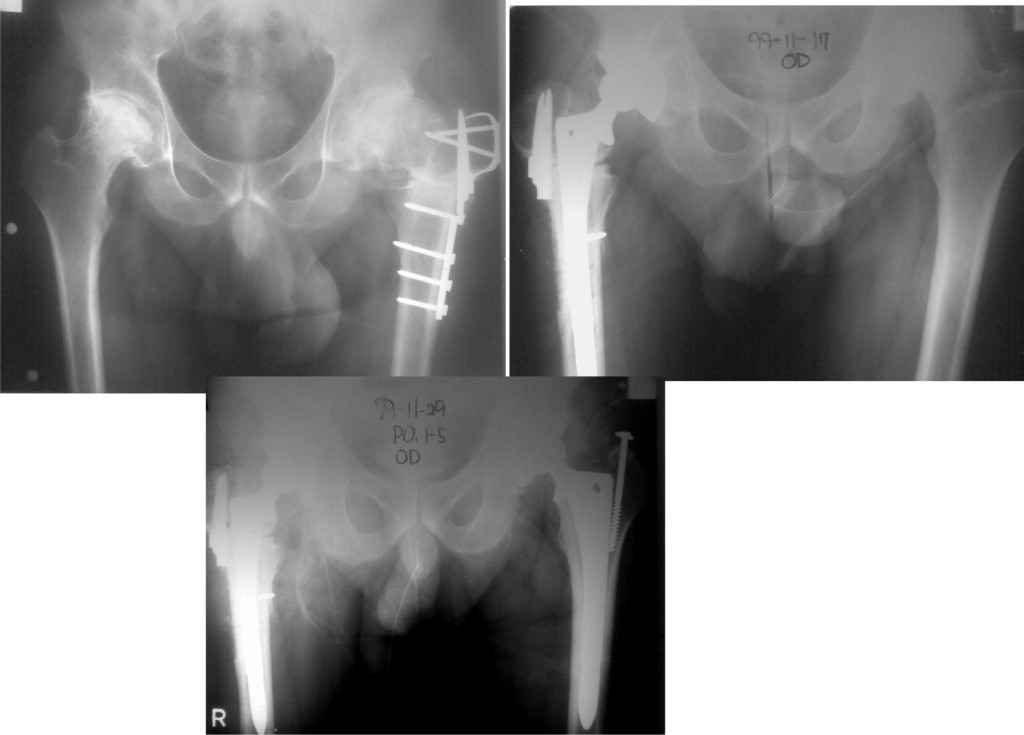

У меня опыт по эндопротезированию совсем небольшой. Еще 5 лет тому назад у нас в городе не было протезирования. Во вложении снимки одного больного из нашего города. который оперировался в 1999 году в Южной Корее. разница по времени замены второго сустава 11 дней. Больной по настоящее время ходит без проблем, особых жалоб не предъявляет, весит он 98 кг. Может быть есть смысл подождать, по наблюдать а оперировать никогда не поздно.

К сожалению на снимках чашки просматриваются плохо. Вопрос: слева в бол. вертеле винт(на снимках после ТЭП). Это доступ с отсечением или что?

дело в том,что на снимках после замены второго сустава прослеживается ход дренажной трубки, т.е снимок контрольный сразу же после операции. Если этот доступ был с отсечением большого вертела, то не прослеживается линия остеотомии. По началу я тоже так и подумал, я считаю, что винт выполняет роль клина для стабильности ножки. Что касается качества снимков то согласен, но судя по контурам вертлужного компонента он напоминает ваш снимок.